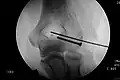

Elastisch stabile intramedulläre Nagelung (ESIN)

Diese Modifikation des Verfahrens mit Bündelnägeln wird heute fast ausschließlich bei Kindern und Jugendlichen mit offenen Wachstumsfugen verwendet. Das Verfahren hat sich aus der Anwendung der Endernägel entwickelt. Im Gegensatz zu den bei Erwachsenen verlassenen intramedullären Drahtnagelungen bewährt sich die ESIN (Synonyme: Prevot-Nagelung, Nancy-Nagelung) bei Patienten im Wachstum aufgrund der besseren Frakturheilung und wegen der einfachen und zuverlässigen Anwendung.

Es handelt sich bei den Implantaten um biegsame elastische Nägel aus Edelstahl oder Titan, die an ihrer Spitze eine Abflachung und eine Abwinkelung tragen, um in der Markhöhle von Röhrenknochen zu gleiten und sich durch die elastische Spannung in der Markhöhle zu verklemmen. Bei geeigneten Brüchen aller großen Röhrenknochen (Oberschenkel, Schienbein, Oberarm, Speiche und Elle) wird durch einen kleinen Hautschnitt in Nähe aber unter Schonung der Wachstumsfuge die Markhöhle des Knochens mit einer Ahle eröffnet. Durch diese Öffnung wird in absteigender oder aufsteigender Richtung ein erster elastischer Nagel eingeführt. Er wird mit drehenden Bewegungen über die Bruchregion geschoben, die unter Röntgensicht korrekt geschlossen oder bei Nicht-Reponierbarkeit offen durch einen Schnitt eingerichtet wird. Die aufgebogene Spitze kann auch als Hilfe bei der Einrichtung (Repositionshilfe) genutzt werden. Unter weiterem Vorschieben verankert sich der Nagel endgültig kurz unterhalb der jeweiligen anderen Wachstumsfuge des Röhrenknochens. Zur ausreichenden Stabilisierung wird mit Ausnahme bei den paarigen Unterarmknochen ein zweiter (oder selten auch ein dritter) Nagel durch einen separaten Zugang in gleicher Verlaufsrichtung eingeführt.

Wenn beide Nägel eingeschlagen sind, werden sie mit einem Bolzenschneider gekürzt, so dass sie unter der Haut verschwinden, aber noch ausreichend lang aus dem Knochen stehen, damit sie wieder zu entfernen sind. Meist wird die Versorgung von beiden Seiten einer Extremität (innen und außen) durchgeführt, es können aber auch beide Nägel z. B. am Oberarm von seitlich absteigend eingeführt werden, wenn auf der Innenseite Gefäße oder Nerven durch die Implantation gefährdet wären. Die ESIN erreicht bei Kindern und Jugendlichen bei geeigneten Brüchen eine gute Übungsstabilität und früh eine Belastungsstabilität. Eine zusätzliche Gipsbehandlung ist nicht notwendig. Die Nägel können durch einen ebenso kleinen Hautschnitt nach wenigen Monaten wieder entfernt werden.

- Fallbeispiele

-

Mit ESIN versorgter schultergelenknaher Oberarmbruch beim Kind. Ausheilungsbild mit deutlich sichtbarem Frakturkallus (Pfeil) -

Komplette Unterarmschaft-fraktur beim Kind mit deutlicher Knickbildung -

Versorgung derselben Fraktur mit je einem Prevot-Nagel (ESIN) in Radius und Ulna